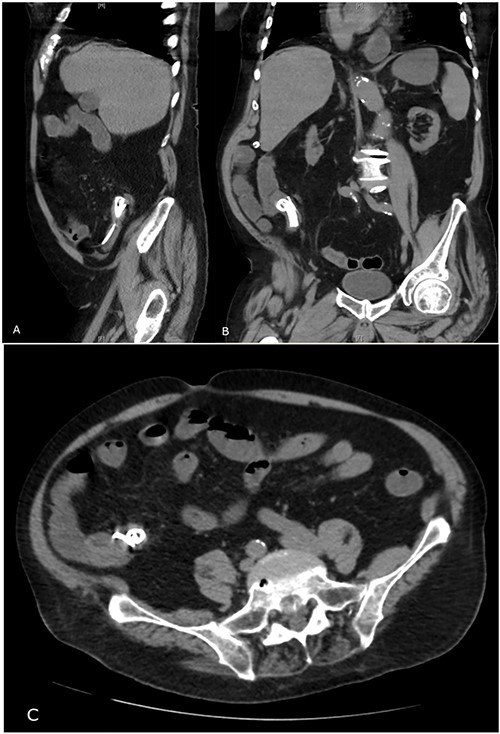

On presentation, there was no signs of shock, with a blood pressure of 152/70, heart rate of 88 and oxygen saturations of 94% on room air. A temperature of 38.1°C, however, was noted and physical examination revealing a distended abdomen with right lower quadrant tenderness. He had no peritonism and digital rectal examination showed an empty rectum. Biochemical investigations showed a white blood cell count of 20.00 × 109/L, C-reactive protein level of 126 mg/L, eGFR of 32 ml/min/1.73 m2, creatinine of 153 umol/L; he had normal liver function tests, coagulation profile and electrolytes. A computed tomography (CT) abdomen and pelvis with intravenous contrast revealed a distally migrated metallic biliary stent located in the terminal ileum with mildly dilated loops of distal small bowel indicating early or incomplete small bowel obstruction (Fig. 2).

Abdominal CT showing migrated biliary stent in sagittal (A), coronal (B) and transverse (C) views.